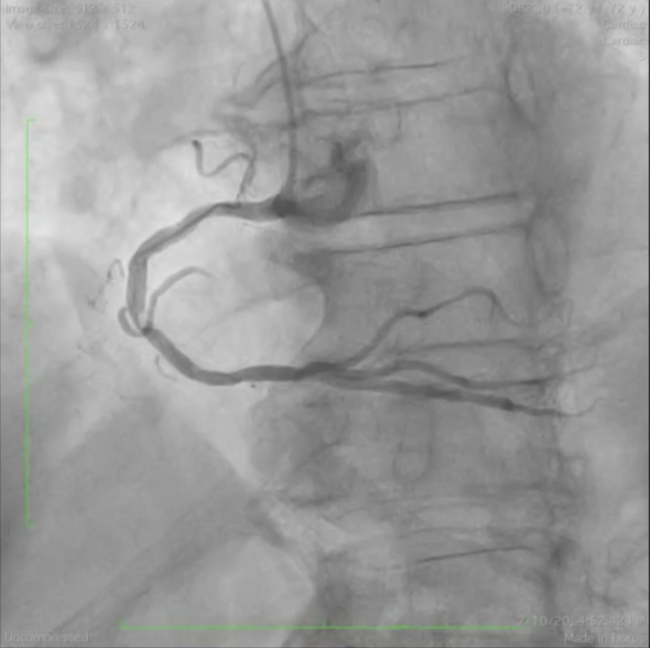

A 72-year-old man was referred for coronary angiography due to worsening exertional angina. Coronary angiography showed consecutive and heavily calcified subtotal stenoses in the mid right coronary artery (RCA) (Figure 1A). As the stenoses were uncrossable by a 1.2 mm balloon, ad hoc rotational atherectomy with a 1.25 mm burr was performed (Figure 1B), followed by implantation of a 3.0 x 38 mm everolimus-eluting stent, which was postdilated with a non-compliant 3.5 mm balloon (Figure 1C). The patient’s angina resolved completely post procedure.

One month later, the patient was admitted due to unstable angina. Coronary angiogram demonstrated a significant stenosis with a non-occlusive thrombus within the stent, along with loss of the stent’s integrity at the mid RCA just after the origin of the right ventricular branch (Figure 1D and Figure 1E; Video 1). Intravascular ultrasound (IVUS) revealed a fractured stent with significant stent recoil (Figure 1F; Video 2). After dilation with a 3.5 mm balloon, we deployed a 3.5 x 13 mm thin-strut sirolimus-eluting stent with bioabsorbable polymer, with excellent angiographic result. Final IVUS showed excellent apposition and expansion of the overlapping stents (Figure 1G and Figure 1H; Video 3). The patient was entirely asymptomatic at the 3-month follow-up exam.